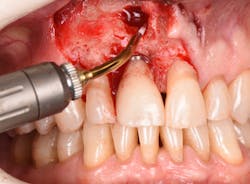

Figure 19: Immediately after incisions and raising a full-thickness flap, suppuration was noted on the apex area of the implant.

Figure 20: An osteotomy was done to access apical area of implant No. 8 utilizing the Er:YAG laser at 20 pps/70 mJ. The then-exposed area was irradiated using a combination of detoxification and biostimulation of the bone and implant to prepare the area to receive a bone graft.